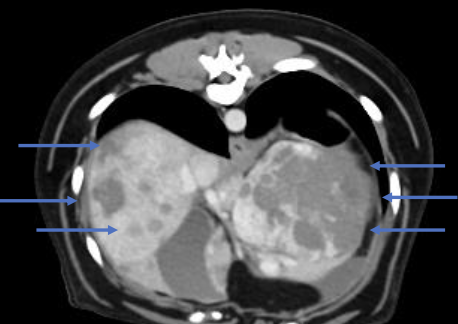

what is the appearance of hemangiosarcoma lesions in the abdomen using abdominal ultrasound?

-heterogenous (hypoechoic to targetoid to mixed)

-cavitation

- +/- peritoneal effusion